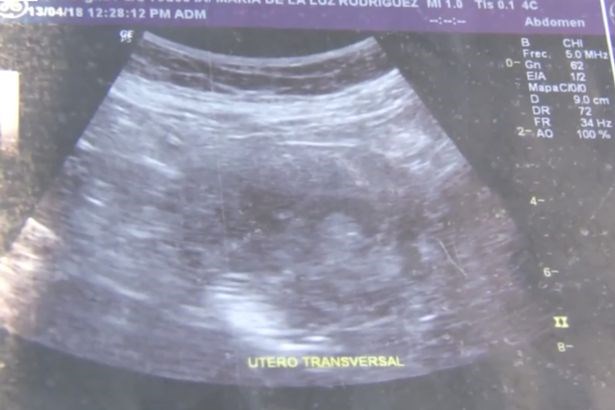

Мария де ла Луз показа на местните медии снимки от ултразвук, които според нея доказват, че е бременна и очаква момиченце.

"Казаха ми, че е момиче. Виж, можеш да видиш малкото й лице", казва тя.

"Краката ме боляха и аз повръщах и се чувствах замаяна. Направиха ми около 10 ултразвука в частна клиника и в (обществената) болница. Лекарите не можеха да повярват", казва тя пред репортерите.